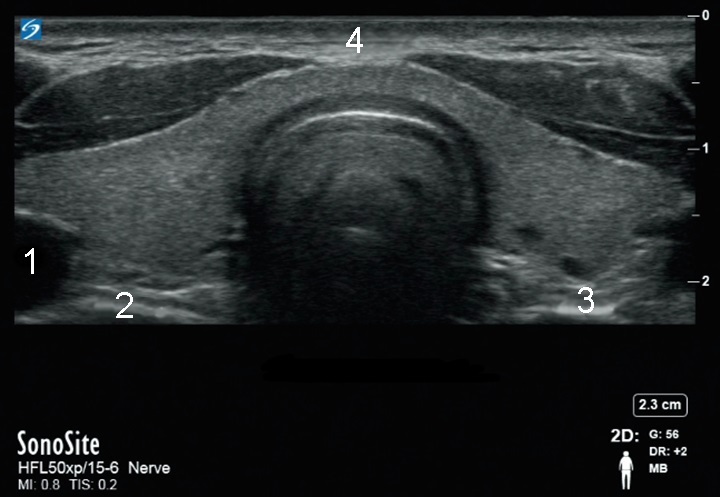

Imagen X-Porte transversal del tiroides

Lóbulo derecho

Lóbulo izquierdo

Itsmo